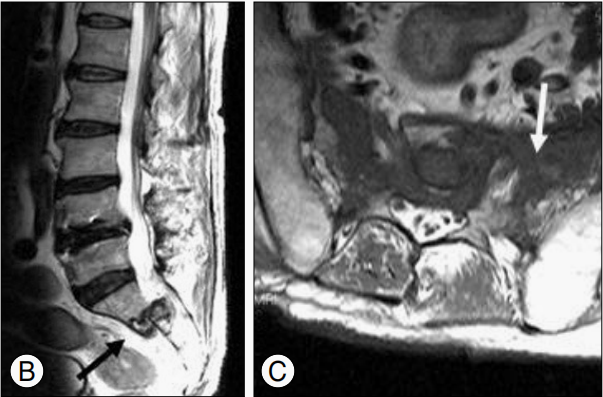

CASE 2

图 3 Case 2. MR T1WI 及增强扫描显示双侧骶骨异常信号伴强化(蓝色直箭头);全身骨显像显示骶骨骨折呈特征性「H」征,CT 示骶骨骨折处骨质不均匀增高、硬化。

CASE 3

图 4 Case 3. MR T1WI 及增强扫描显示骶骨左侧份高信号(蓝色直箭头);FDG-PET/CT 显示双侧骶骨翼对称性摄取 FDG(蓝色弯箭头),CT 图像示骶骨左侧份骨质硬化改变。

图 5 Case 3. 随访 CT 显示骶骨骨折呈不均匀性硬化改变,骨折线可见。随访 MRI 显示骶骨骨折处稍高信号(蓝色直箭头)。骨扫描 ECT 图像可见双侧骶骨翼及髂骨体呈 Tc-99 mMDP 浓聚。